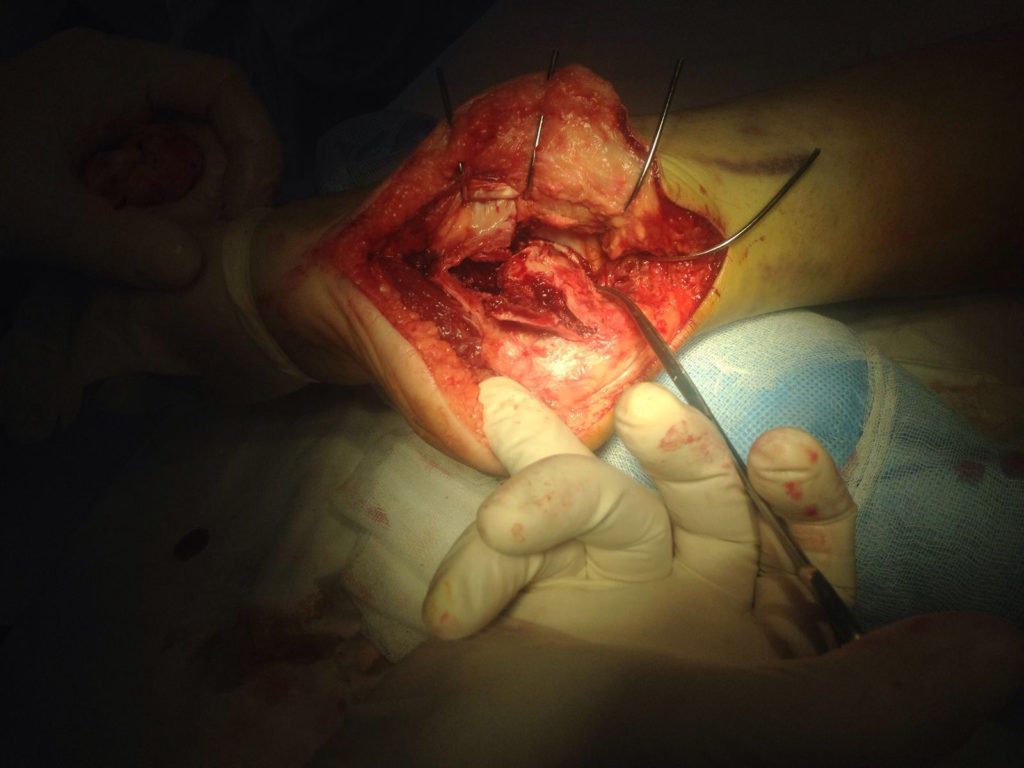

Применение материала Остеоматрикс при импрессионно-оскольчатом переломе пяточной кости

Операция – открытая репозиция, остеосинтез пяточной кости пластиной с костной ксенопластикой материалом «Остеоматрикс». На контрольных снимках в три месяца имеется консолидация перелома, миграции фиксатора нет, имеется остеоинтеграция ксенопластического материала.